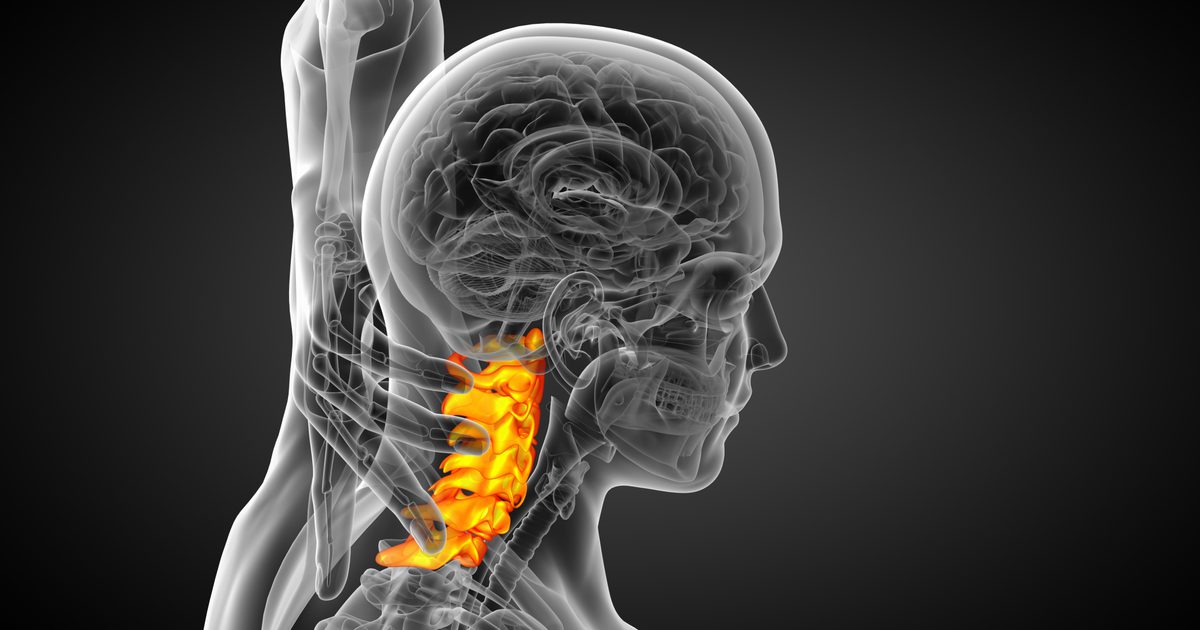

Vertebrae

Spinal injuries can cause major issues in a person’s lifestyle, and dealing with spine issues can be a very delicate process on the part of the doctor. One slip up could mean affecting a person’s ability to walk or even use their arms and fingers.

Fortunately, advances have been made that provide possible solutions for some of these issues. With the capability of making exact replicas of a damaged or shifting spine, doctors can make more accurate analyses of what kind of treatment would be best for the patient, without putting them at risk. More recently, surgeries have actually been done giving people new vertebrae created from a 3-D printer.